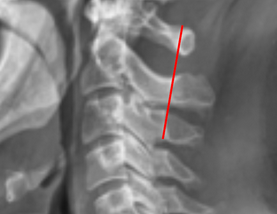

Image Type Cervical Spine X-Ray CT Scan MRI Scan Atlantodental Interval (ADI) Basion-Axial Interval Basion-Dens Interval (BDI) C2 Tilt C2–C7 Coronal Cobb Angle Cervical C2-7 lordosis C2-C7 Translation Chamberlain’s Line / McGregor’s Line Flexion-Extension George’s Line (Posterior Cervical Line) K-Line Interpedicular Distance (IPD) Occiput-C2 Angle Occipital Condyle–C1 Interval (CCI) Posterior Atlantodental Interval (PADI) Power’s ratio Sagittal Canal Diameter Sagittal Vertical Axis (SVA) Spinolaminar line Swischuk Line T1 Slope Torg/Pavlov Canal-to-Body Ratio